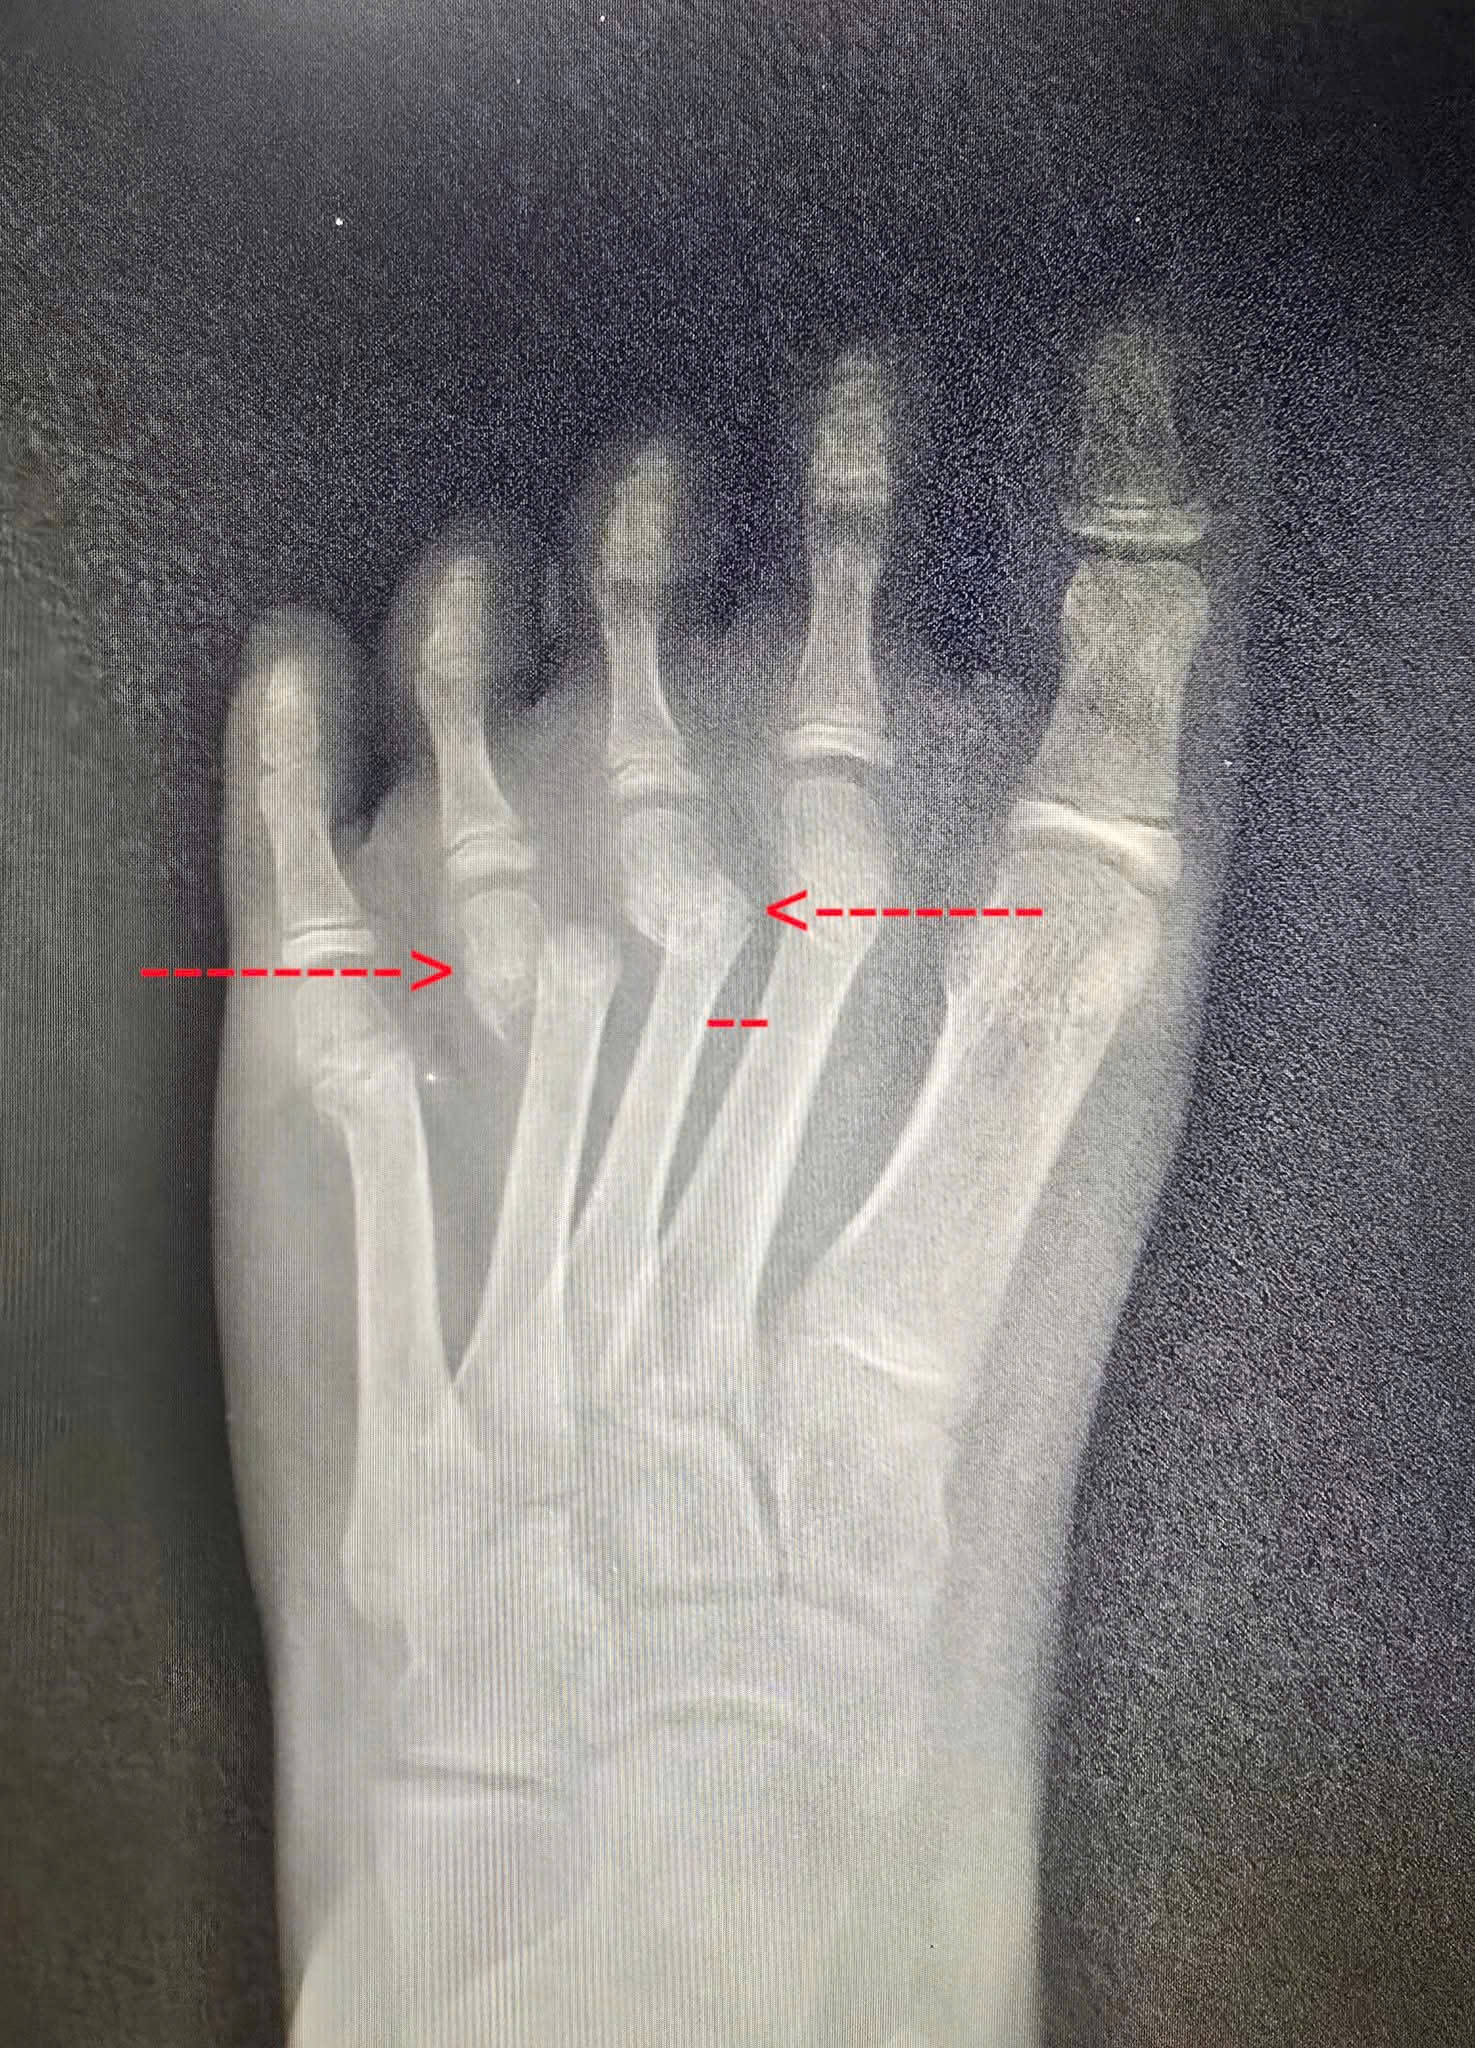

❤️ Bệnh nhân nữ, 8 tuổi không may bị trượt chân té ngã gãy kín xương bàn 2 đến 5 bàn chân trái. Bé được 1 phòng khám lớn cho bó bột và dặn 4 tuần bỏ bột không hẹn tái khám. Bệnh nhân về thấy còn đau, sưng người nhà đưa đến Trung tâm y tế Thành phố Thuận An được các Bác sĩ chuyên khoa Chấn thương chỉnh hình khám, x quang kiểm tra thấy xương bàn 3 và 4 còn di lệch nhiều cần phải phẫu thuật nắn chỉnh lại. Từ khi Bệnh nhân bị tai nạn đến khi mổ là gần 10 ngày xương gãy đã có nhiều cal xương nên các Bác sĩ phải phá cal và kết hợp xương xuyên kim Kirschner để cố định xương gãy. Kết quả sau mổ xương gãy đã được nắn chỉnh hết di lệch, giúp xương lành tốt và không ảnh hưởng đến chức năng sau này của bàn chân.